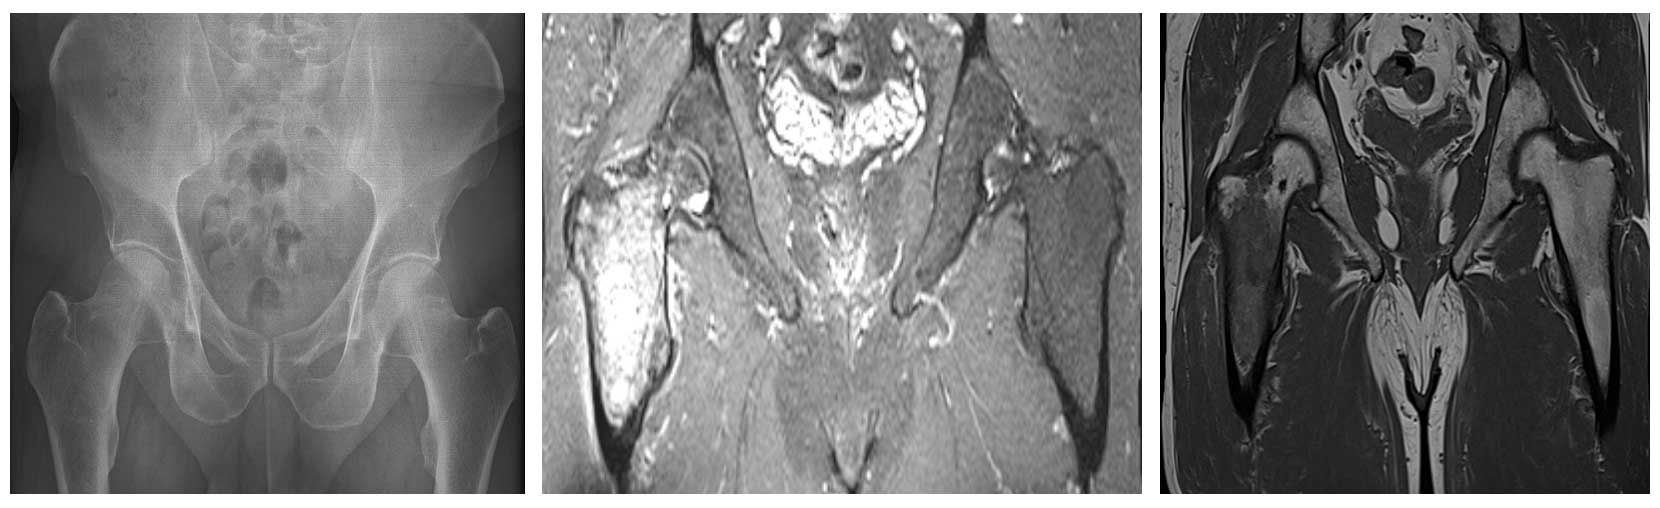

Ameliyat Öncesi: Röntgende litik lezyon, MR’da düzensiz sınırlı heterojen kitle ve çevreleyen ödem görülmekte.